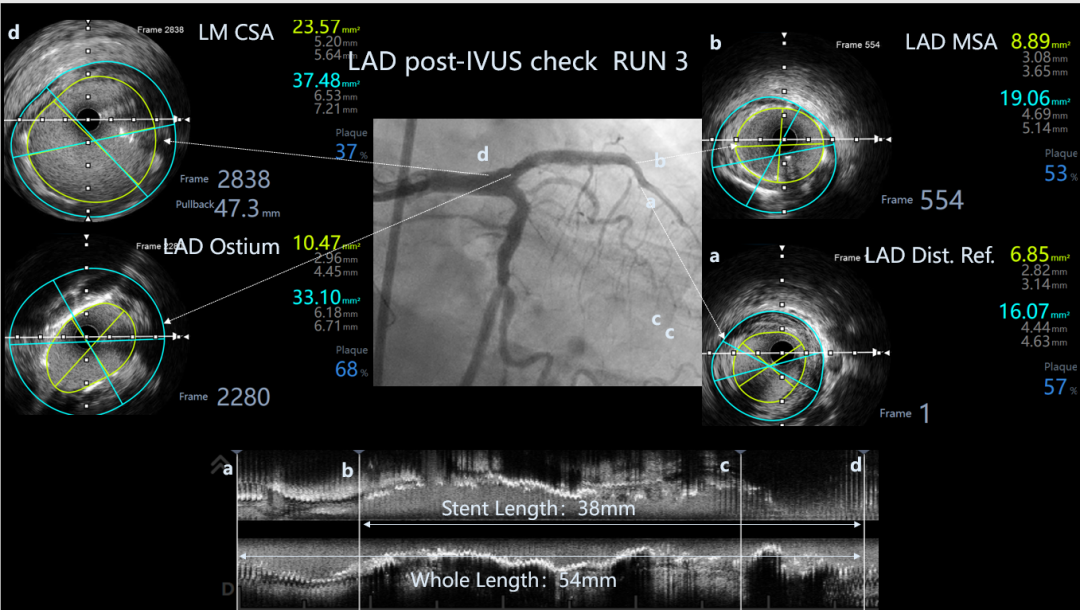

LAD post-IVUS check RUN 3

Final result: TIMI flow grade 3

首选IVUS找开口、因LM直径达6.5mm,无法看清分支方向。